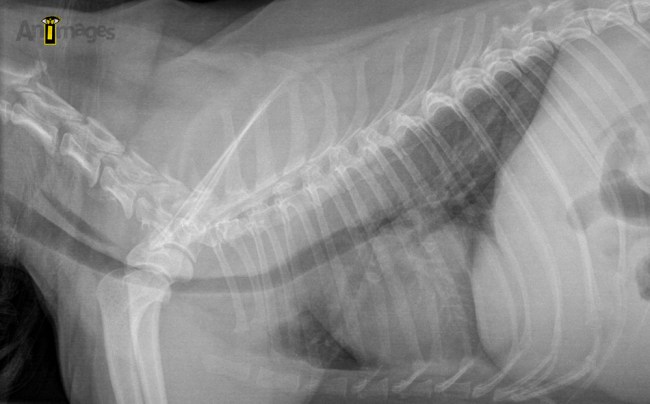

Sur la projection latérale ci-haut, la lumière trachéale est légèrement irrégulière et réduite en portion thoracique crâniale, mais sans évidence de collapsus. L’absence de collapsus sur ce cliché pourrait nous inciter à chercher ailleurs pour expliquer la toux… Mais au lieu de tomber dans ce piège, un fluoroscopie a été recommandée!